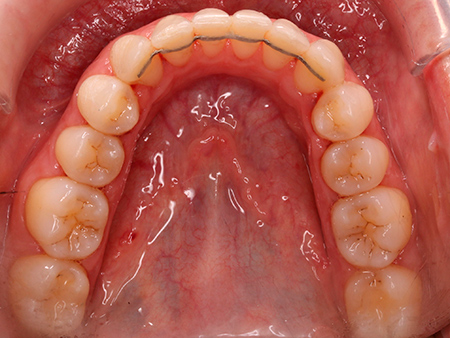

Ortodoncia con brackets linguales Incognito

Después de analizar su caso, nuestras ortodoncistas le recomendaron abordar un tratamiento de ortodoncia con brackets linguales Incognito. Su objetivo era corregir la sobremordida, el apiñamiento y la mordida en tijera que Mireia presentaba en un inicio.

Tras un tratamiento de ortodoncia con brackets Incognito de 18 meses de duración, Mireia goza de una oclusión óptima y, además, ya disfruta de la sonrisa que siempre había deseado.